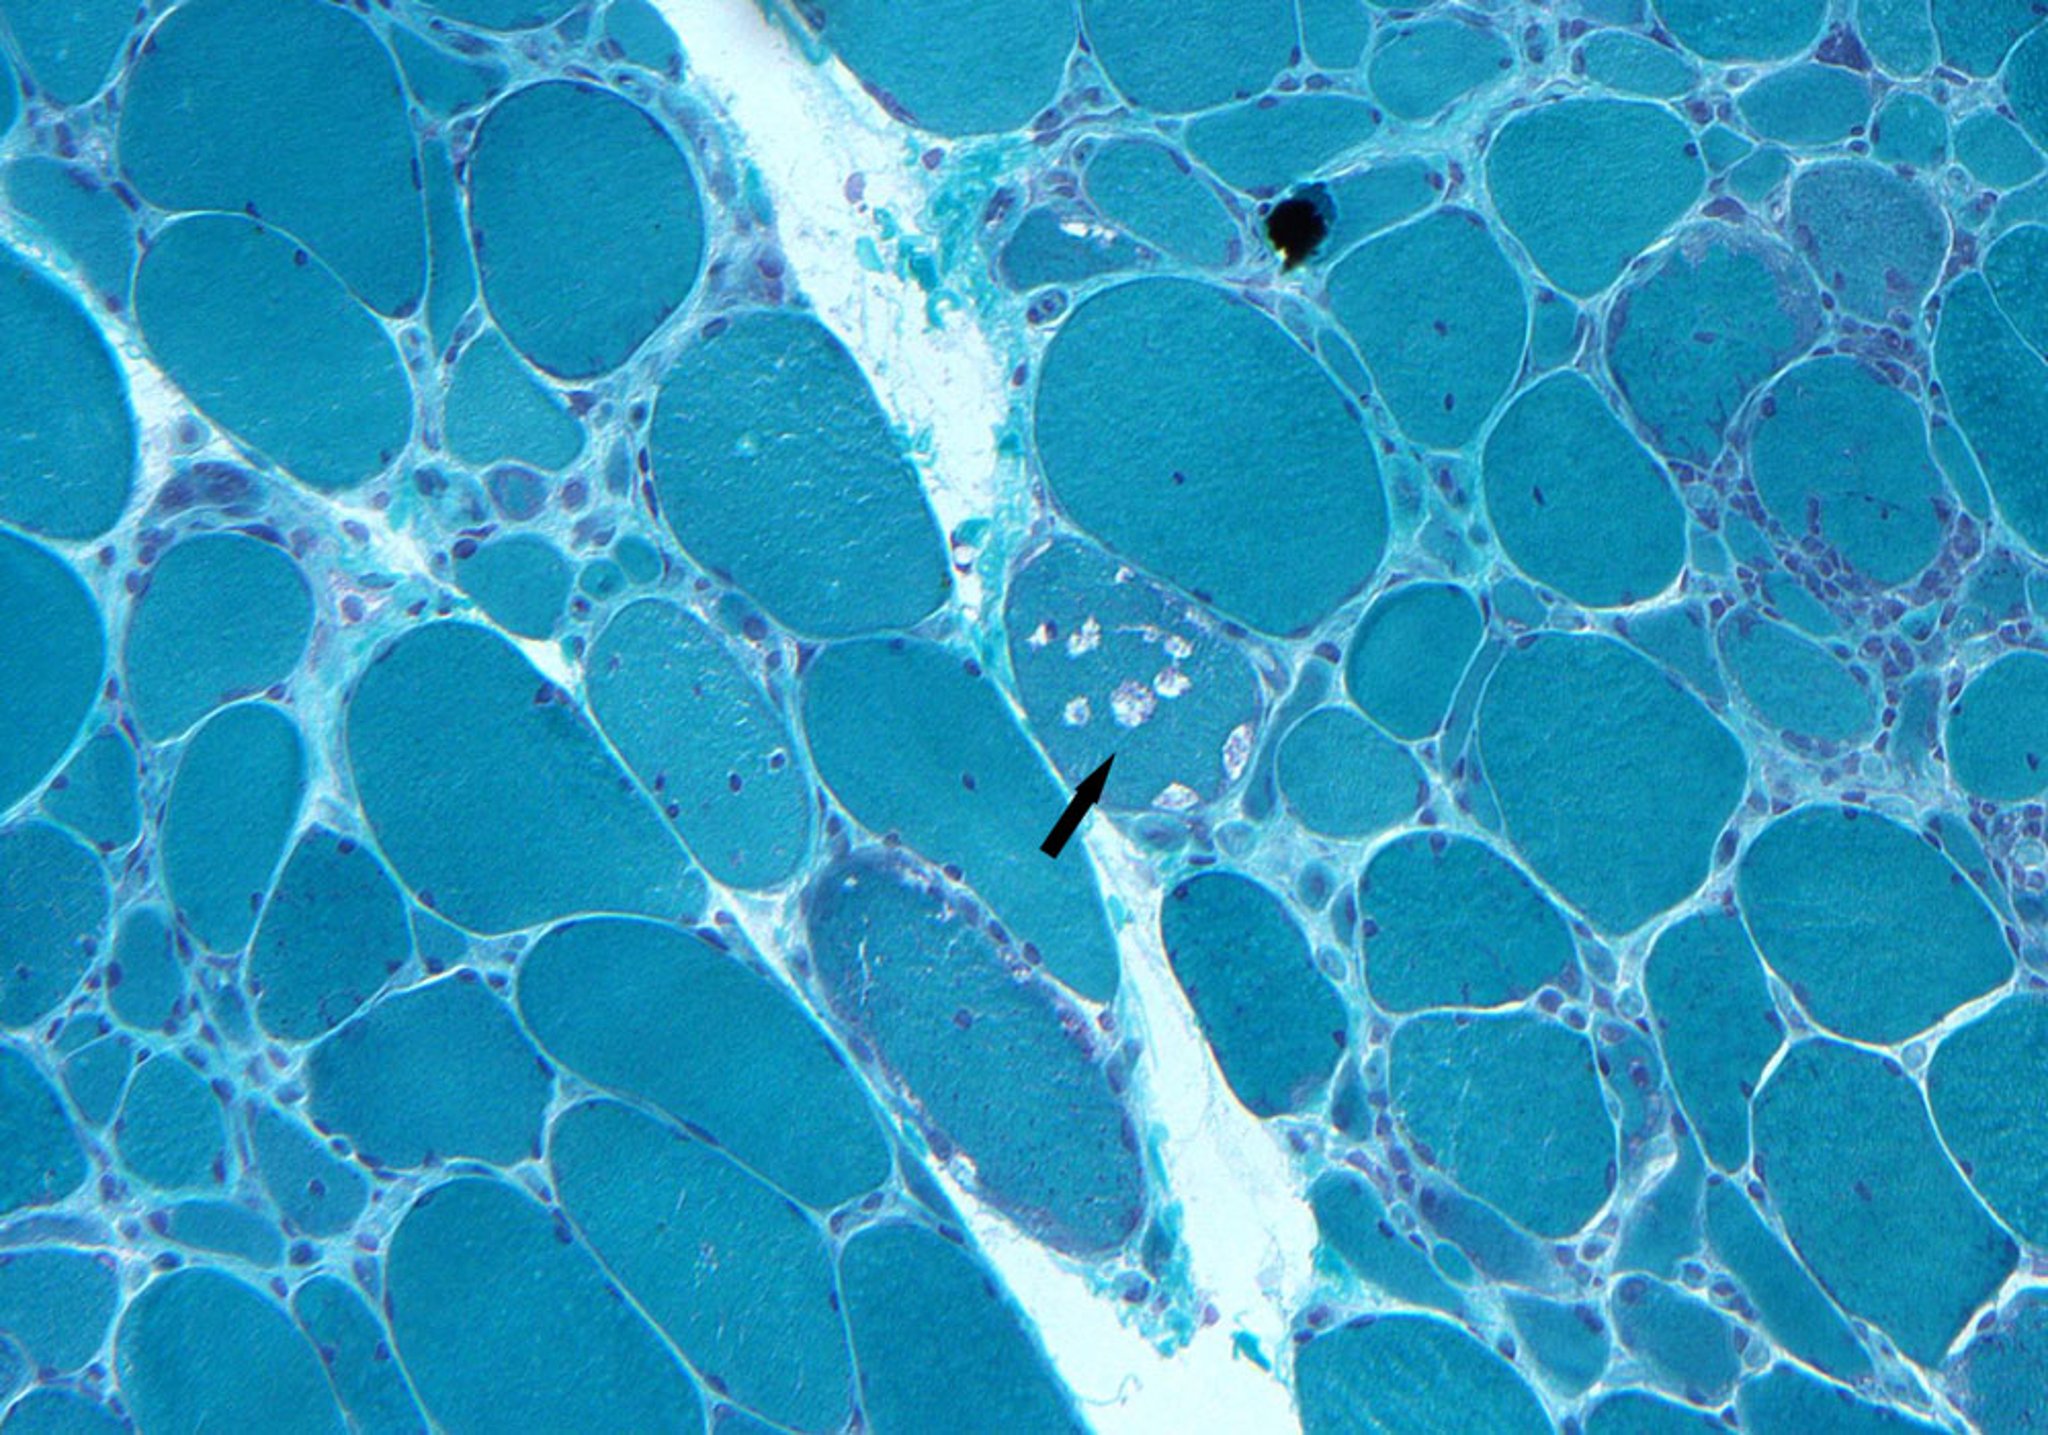

Inclusion Body Myositis

This biopsy specimen shows endomysial infiltrates, myofiber degeneration, and rimmed vacuoles (arrow).

Photo courtesy of Kinanah Yaseen, MD.